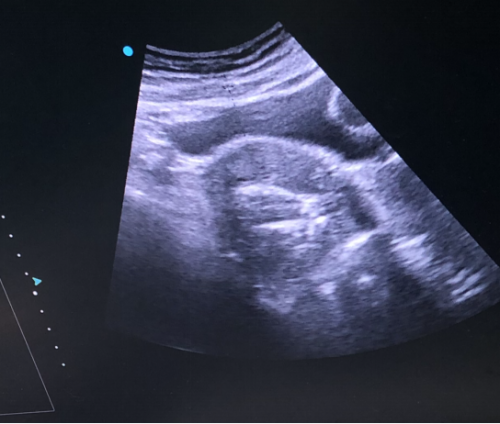

术后:

微波消融后肌瘤病灶内会发生凝固性坏死,即刻超声造影就可以看到病灶内没有造影剂充填。磁共振增强扫描病灶内呈现充盈缺损,增强后呈黑色区域,表示病灶坏死区域。坏死的病灶随时间推移,会逐渐萎缩吸收,子宫体积也会有一定的缩小,从而使痛经、月经量多等临床症状得到缓解和改善。